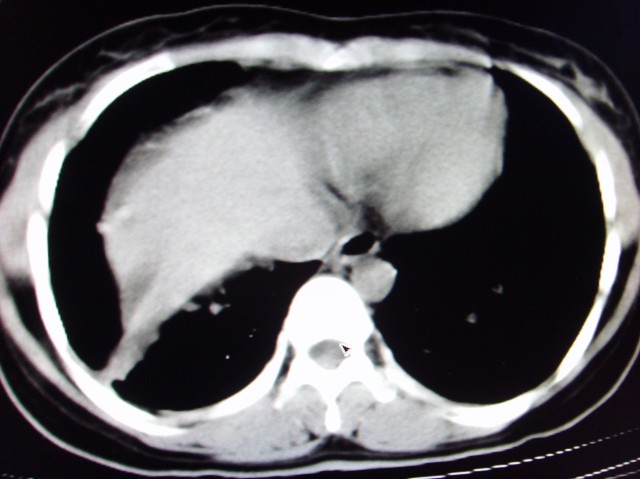

标题: CT7125:中央性肺Ca.

还有肺不张

中央型肺癌伴阻塞性肺炎

经典病历,肿块。肺内转移、淋巴结转移。胸膜仗义

首先考虑中央型肺癌伴阻塞性肺炎双肺、淋巴结转移,可以正规抗炎治疗一周后复查